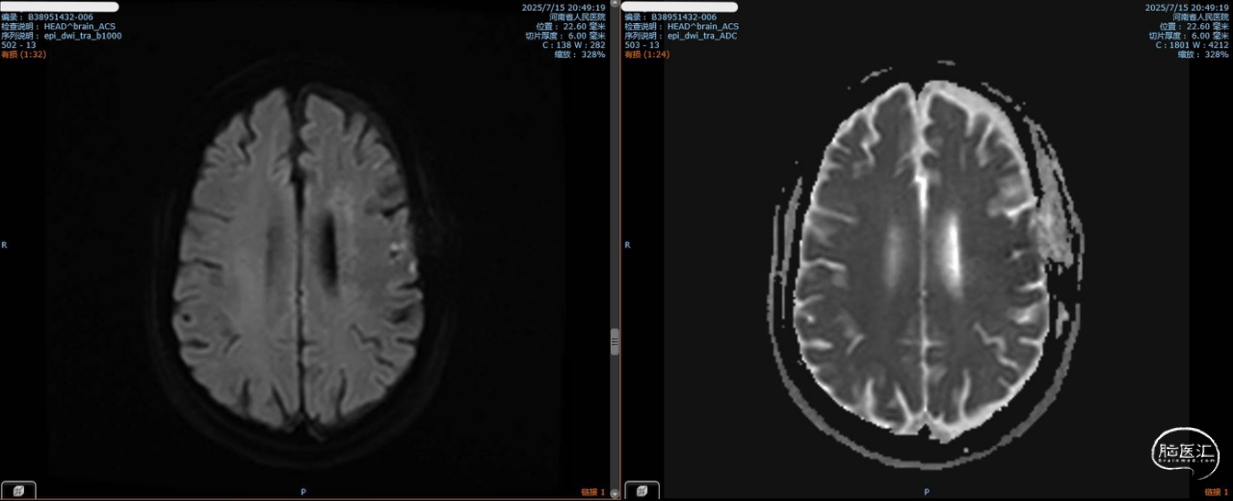

2025-7再次入院,术前MRI无急性期脑梗死。

术后第七天,头部MRI提示左侧额顶叶急性脑梗死。